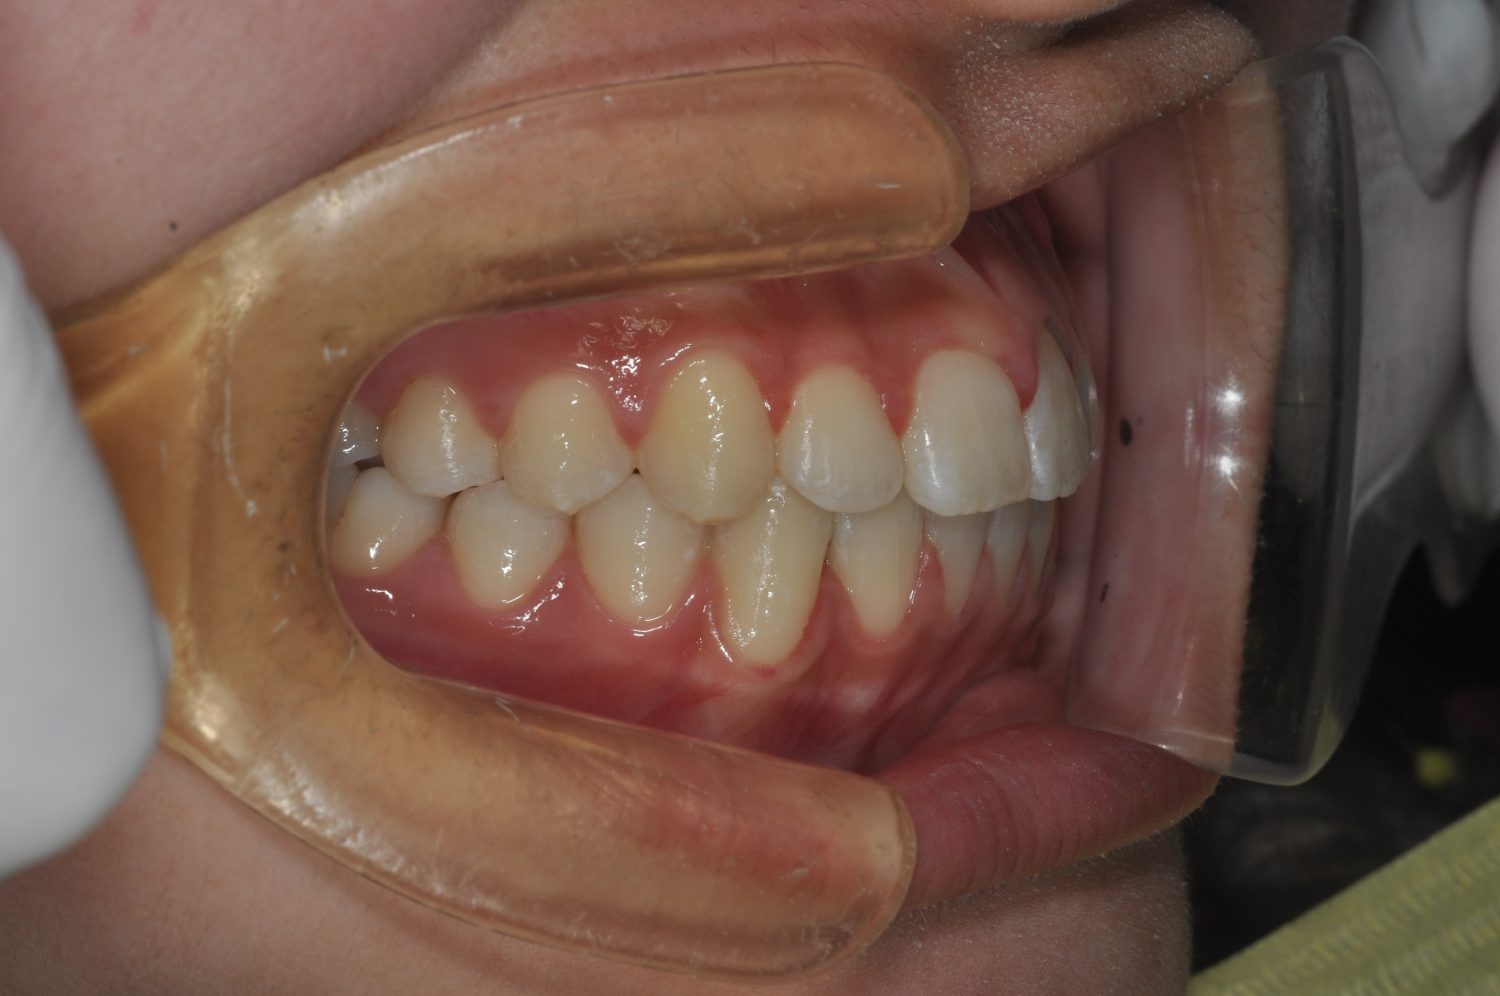

| 主訴 | 前歯部の叢生と正中の不一致 |

| 治療内容 | 軽度の叢生の改善を行うために、非抜歯でのマルチブラケット装置による治療を行った。 |

| 治療費 | Ⅱ期治療費:275,000円(税込) 調整料 5,500円(税込)×18回 保定時:22,000円(税込) 計 396,000円(税込) |

| 治療期間 | 2年2ヶ月 |

| 治療回数 | 20回 |

| 想定されたリスク | 矯正後に後戻りする可能性がありました。 |

Ⅰ期治療で叢生、反対咬合の改善をセクショナルアーチとMPAを使用して改善した後、成長観察を行っていました。永久歯の萌出したため、Ⅱ期治療を開始することとなった。上下顎とも骨格的に問題がなかったため、非抜歯で治療を行った。